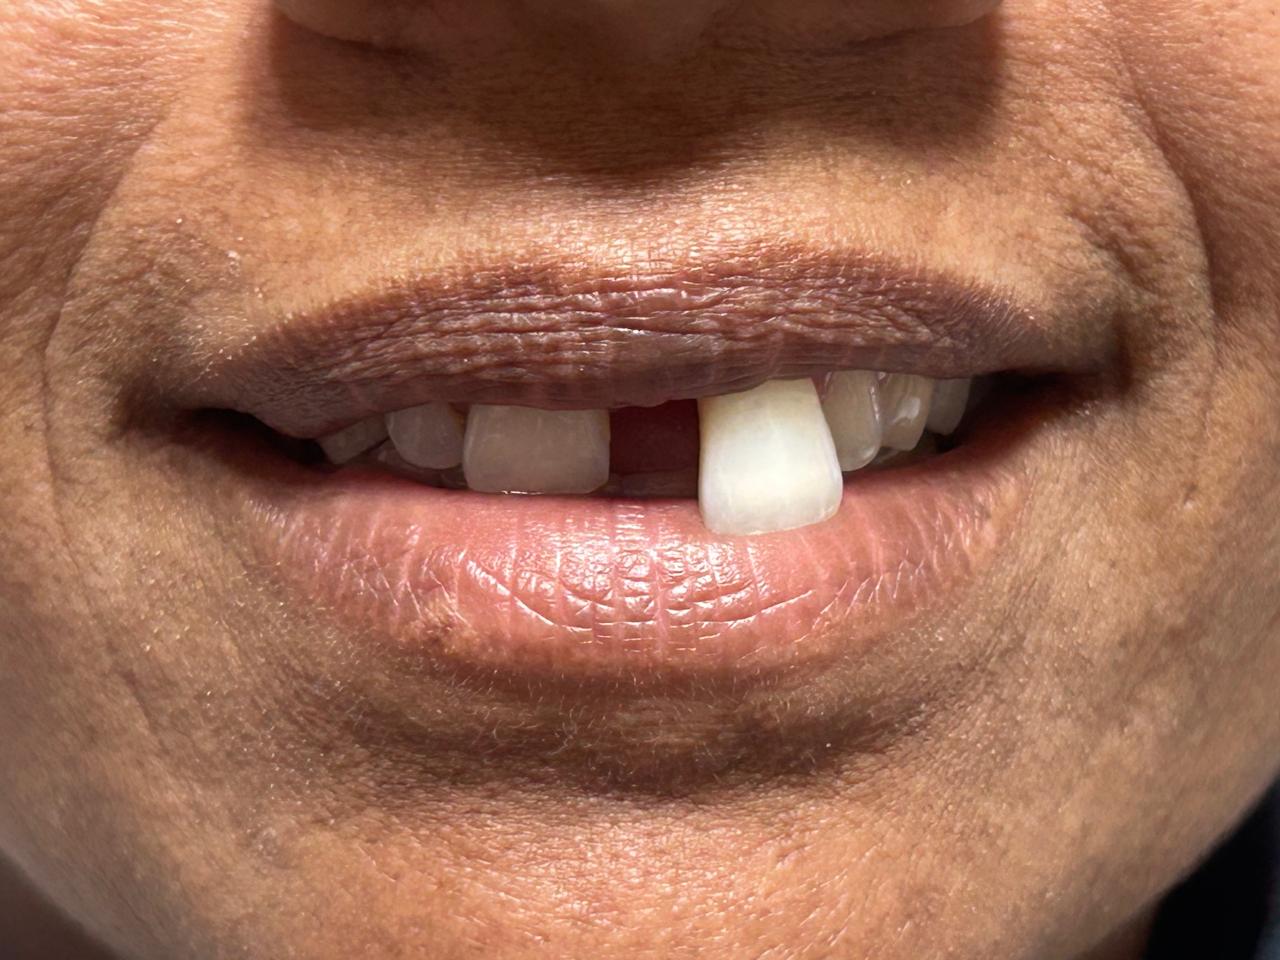

Bleeding Gums

Are you noticing bleeding gums when you brush or floss? This common issue can signal more than just a minor inconvenience, and at NG Dental and Health, we are dedicated to helping you tackle it head-on.

Our skilled team is ready to provide you with the compassionate care you deserve, ensuring that your gum health is prioritized. We take the time to thoroughly assess your situation and craft a tailored treatment plan that addresses your unique needs. With our emphasis on education and prevention, we empower you to take control of your oral health journey.

Don’t let bleeding gums hold you back from smiling confidently. Reach out to us today and take the first step towards healthier, happier gums.